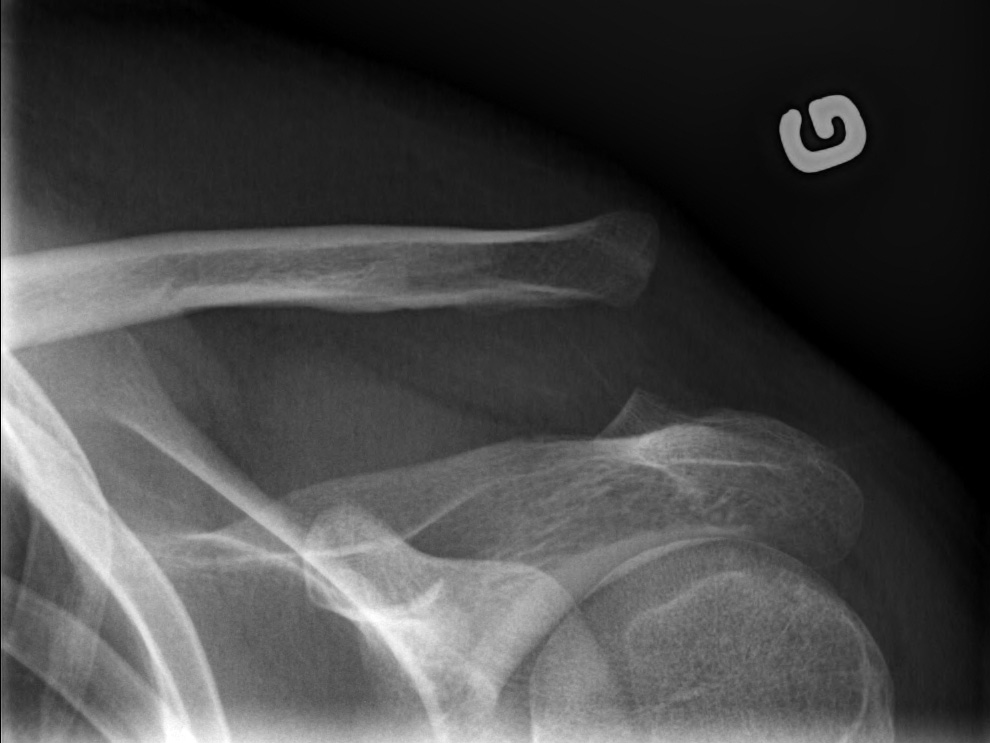

27-year-old male:

Left shoulder pain following a direct fall on the shoulder.

Acromioclavicular luxation

Bone misalignment

The left clavicule is displaced superiorly with increased acromioclavicular and coracoclavicular distance relative to the right side.

Displacement measurement

Superior displacement of the left clavicle with a coracoclavicular distance of 32 mm compared to 13 mm on the right side (146% displacement). This is thus a grade 5 acromioclavicular joint dislocation.